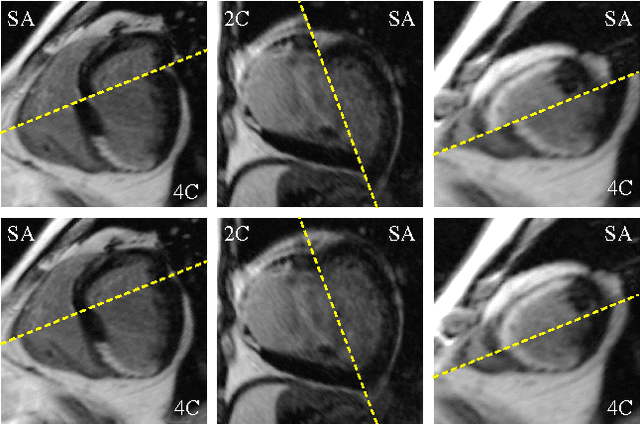

Abstract:Late gadolinium enhanced (LGE) cardiac magnetic resonance (CMR) can directly visualize nonviable myocardium with hyperenhanced intensities with respect to normal myocardium. For heart attack patients, it is crucial to facilitate the decision of appropriate therapy by analyzing and quantifying their LGE CMR images. To achieve accurate quantification, LGE CMR images need to be processed in two steps: segmentation of the myocardium followed by classification of infarcts within the segmented myocardium. However, automatic segmentation is difficult usually due to the intensity heterogeneity of the myocardium and intensity similarity between the infarcts and blood pool. Besides, the slices of an LGE CMR dataset often suffer from spatial and intensity distortions, causing further difficulties in segmentation and classification. In this paper, we present a comprehensive 3-D framework for automatic quantification of LGE CMR images. In this framework, myocardium is segmented with a novel method that deforms coupled endocardial and epicardial meshes and combines information in both short- and long-axis slices, while infarcts are classified with a graph-cut algorithm incorporating intensity and spatial information. Moreover, both spatial and intensity distortions are effectively corrected with specially designed countermeasures. Experiments with 20 sets of real patient data show visually good segmentation and classification results that are quantitatively in strong agreement with those manually obtained by experts.

Abstract:Automatic segmentation of the left ventricle (LV) in late gadolinium enhanced (LGE) cardiac MR (CMR) images is difficult due to the intensity heterogeneity arising from accumulation of contrast agent in infarcted myocardium. In this paper, we present a comprehensive framework for automatic 3D segmentation of the LV in LGE CMR images. Given myocardial contours in cine images as a priori knowledge, the framework initially propagates the a priori segmentation from cine to LGE images via 2D translational registration. Two meshes representing respectively endocardial and epicardial surfaces are then constructed with the propagated contours. After construction, the two meshes are deformed towards the myocardial edge points detected in both short-axis and long-axis LGE images in a unified 3D coordinate system. Taking into account the intensity characteristics of the LV in LGE images, we propose a novel parametric model of the LV for consistent myocardial edge points detection regardless of pathological status of the myocardium (infarcted or healthy) and of the type of the LGE images (short-axis or long-axis). We have evaluated the proposed framework with 21 sets of real patient and 4 sets of simulated phantom data. Both distance- and region-based performance metrics confirm the observation that the framework can generate accurate and reliable results for myocardial segmentation of LGE images. We have also tested the robustness of the framework with respect to varied a priori segmentation in both practical and simulated settings. Experimental results show that the proposed framework can greatly compensate variations in the given a priori knowledge and consistently produce accurate segmentations.